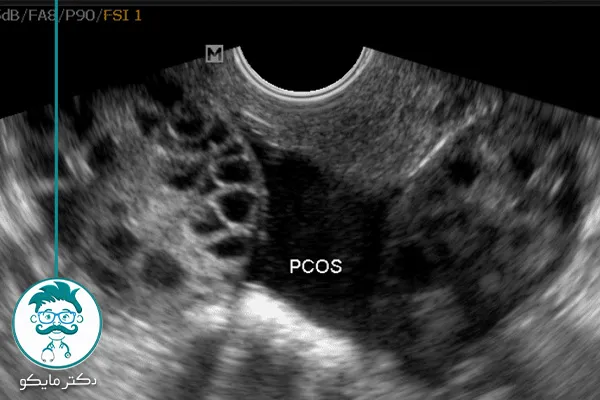

ممکن است برای شما نیز این سؤال پیش آمده باشد که سندرم تخمدان پلی کیستیک چیست؟ کیست تخمدان یا پلی کیستیک یک توده شبیه به حبه یا کیسهای است که در داخل یکی از تخمدانها شکل میگیرد. این توده ممکن است شامل مایع، بخشهای جامد یا هر دو باشد. بیشتر کیستهای تخمدان بیخطر هستند و در اکثر موارد به صورت خودبهخود از بین میروند.

کیست تخمدان یا پلی کیستیک یک توده شبیه به حبه یا کیسهای است که در داخل یکی از تخمدانها شکل میگیرد. این توده ممکن است شامل مایع، بخشهای جامد یا هر دو باشد. بیشتر کیستهای تخمدان بیخطر هستند و در اکثر موارد به صورت خودبهخود از بین میروند.